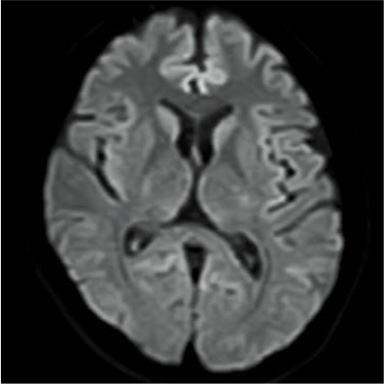

RADAR’ın TOF MRA ve GrE T2*WI’deki etkileri

RADAR, yüksek hassasiyetli sinyal düzeltme teknolojisi kullanılarak GrE sekanslarına uygulanmıştır. Bu, rutin baş incelemelerinde gerekli tüm sekanslar için RADAR’ın kombine kullanımını mümkün kılmıştır.